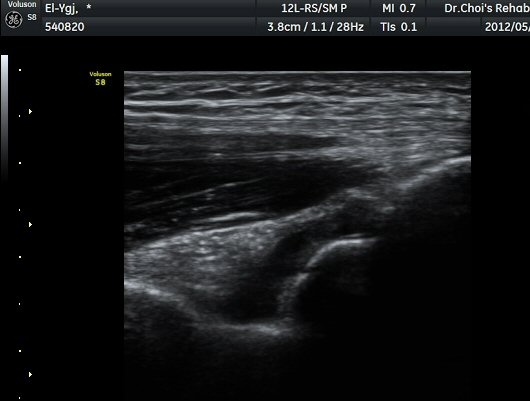

ÁֵοÍ(olecranon fossa) Á¾´Ü¸é°Ë»ç¿Í Ⱦ´Ü¸é°Ë»ç¿¡¼­ ÁÖµÎ¿Í ¼ö¾×Àú·ù¿Í °ø¿¡ÄÚ »À µ¢¾î¸®°¡

°üÂûµÈ´Ù(±×¸² 4, 5, 6).